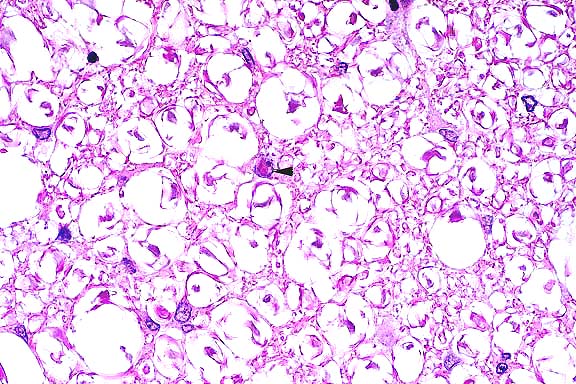

- The giant cell pneumonia seen in this case is typical of

SIVmac-induced giant cell pneumonia and is characterized by extensive

infiltration of alveolar septa and spaces by numerous macrophages

with abundant foamy cytoplasm and multinucleate giant cells of

macrophage-monocyte origin. The interstitial pneumonia with karyomegaly

and intranuclear inclusions is characteristic of cytomegalovirus,

a common secondary infection in SIVmac-infected animals. On transmission

electron microscopy, an unidentified cell in the lung was found

to contain an intranuclear inclusion body with peripheral clearing

of the nuclear chromatin. Dispersing the nuclear chromatin were

viral particles measuring 100 to 110 nm. The viral particle size

and morphology were consistent with those of the herpesviridae

group.

- Case 22-1. Lung. A syncytial giant cell is accompanied

by abundant foamy alveolar macrophages within and thickening

the septal walls (interstitial pneumonia).